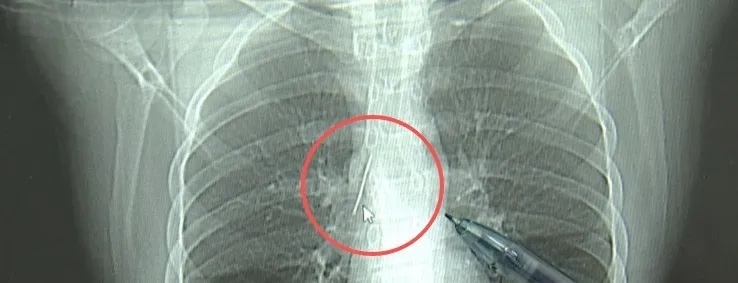

近日,安徽17岁小伙小陆参加征兵体检,胸片结果显示:胸腔内有一处金属高密度影,形态细长,像一根针。

进一步的CT检查确认,异物是一枚金属针,斜插在肺组织内,位置十分凶险

杭州市第一人民医院心胸外科副主任 冯兴“这个针的尖锐部正好指向他体内的一个大血管,边上是上腔静脉和胸主动脉,因此,这个针稍有不慎,就有可能造成周边血管的损伤,甚至危及生命。